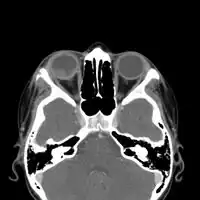

CT chest: Paracoccidioidomycosis -

CT-scan head: Intraorbital enhancing mass lesion and two outer eyelid lesions with necrotic center and enhancing borders.